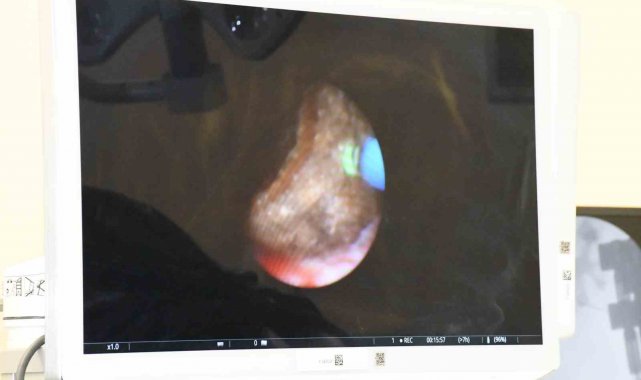

Sol yan ağrısı şikâyetiyle hastaneye başvuran 64 yaşındaki Osman Öztürk'ün yapılan tetkiklerinde sol böbreğin alt kesiminde 2,5 cm'lik taş tespit edildi. Hastanın taşları, sırtüstü yatar pozisyonda (Supine Mini PNL) yaklaşık 3-5 mm'lik bir kesiden girilerek tamamen temizlendi.

Op. Dr. Fatih Kocamanoğlu, Mini-PNL'nin standart PNL'ye göre en önemli avantajının böbreğe daha ince cihazlarla müdahale edilmesiyle böbrek üzerine olan travmanın daha az olduğuna dikkat çekerek, "Sol yan ağrısı şikâyetiyle gelen hastamıza yaptığımız görüntülemede sol böbrek alt klikslerinde yerleşen yaklaşık 2,5 santimetrelik taşının olduğunu gördük. Taşın yeri ve boyutu gözetilerek hastaya tutama ameliyatını yapma kararı aldık. Bu ameliyatta daha minimal invaziv bir cerrahi olan Mini-PNL, yani yaklaşık 3-5 milimetrelik bir kesiden girerek taşları temizlemeyi planladık. Ve bu yöntemi de hastamıza başarıyla gerçekleştirdik. Hastanemizde ilk kez gerçekleştirdiğimiz avantajlarından dolayı da tercih ettiğimiz Spupine yöntemle yani sırtüstü yatar pozisyonda Mini Perkütan Nefrolitotomi'yi hastamıza uyguladık. Hastamıza acil şifalar diliyoruz" dedi.